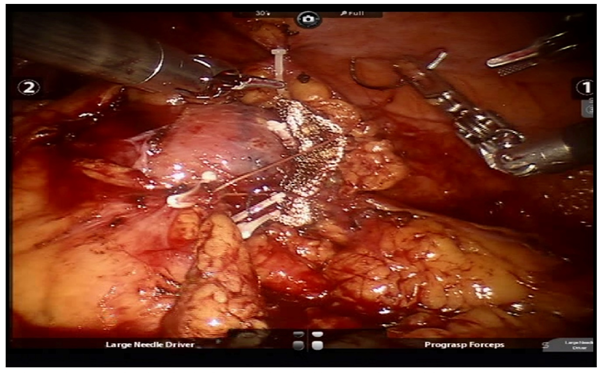

All patients underwent pre-operative contrast-enhanced computed tomography (CECT) of abdomen with renal angiography for tumour and vascular anatomy with 3D reconstruction (Figure 1). Routinely ipsilateral ureteric catheter was placed after anaesthesia. Surgical steps that were sequentially followed in all cases included ipsilateral colonic mobilization along with identification of ureter, gonadal vessels and psoas muscle; identification and mobilization of the renal artery and vein; mobilisation of the upper pole according to the need; demarcation of the tumour boundary with the help of intraoperative ultrasound; hilar clamping (renal artery and vein separately clamped); resection of the tumour; two layered renorrhaphy (Figure 2) with barbed suture with application of haemostatic agents (Gelatin granules with human thrombin and oxidised regenerated cellulose) and peri-renal drain placement. Zero-ischemia RPN were performed premeditatedly for cases with small (<4cm) cortical renal mass (predominantly exophytic) in favourable positions (lateral, lower and upper pole) and where single isolated feeder vessel was well identified (Figure 3). Ipsilateral ureteric catheter was removed routinely on 2nd post-operative day. We replaced the ureteric catheter with double-J stent where pelvicalyceal system were opened intraoperatively or tumour was larger one in vicinity to the pelvicalyceal system.

Figure 3 (a) right upper pole renal mass selected for zero ischemia (b) 3D reconstruction.